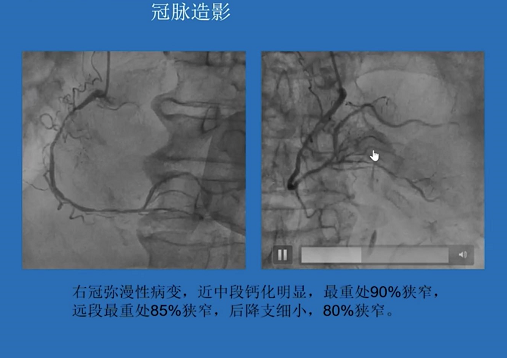

病例一:82岁高龄男性患者,心功能差,冠脉造影显示RCA弥漫病变,近中段钙化明显,最重处狭窄90%;左主干开口90%狭窄,LAD全程弥漫病变,最重处狭窄95%,D1弥漫病变,最重处狭窄95%;LCX弥漫病变且次全闭塞。

患者及家属拒绝外科搭桥手术,遂决定在ECMO支持下进行旋磨。多次旋磨后成功恢复血流,且未见夹层和血肿形成。术后1年复查造影未见明显狭窄,患者生活质量大大改善。